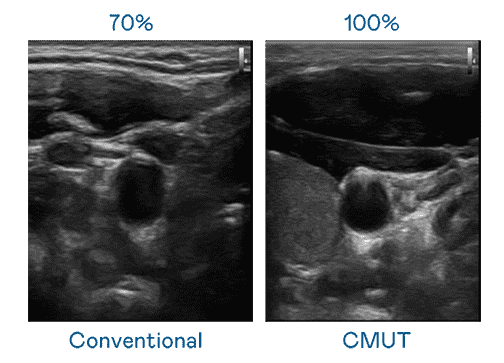

CMUT 技术是一种用电容式微机电元件来产生超音波讯号的技术。。与传统 PZT 压电式技术相比,,CMUT 频宽增加 30%,,,,更宽频的超音波讯号让影像解析度大幅提升,,,,是实现高影像品质医疗超音波扫描、、促进精准医疗发展的关键技术。。

大频宽带来超清晰影像

超音波影像的解析度高低,,首先取决于探头能发出的讯号频宽。。。。z6mg·人生就是博 CMUT 可提供高清晰的超音波讯号,,提供高频宽、、、、高灵敏度、、、影像纹理细节更高的超音波影像,,,,协助医护人员缩短影像判读时间及利用精准的医疗影像进行诊断。。。。